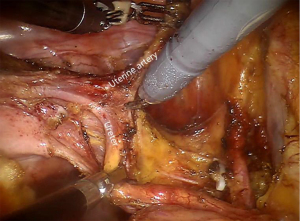

Uterine arteries ligation

The crux of the uterine artery ligation is to make out its anatomical location and dissociate it from the initial part (Figure 5).